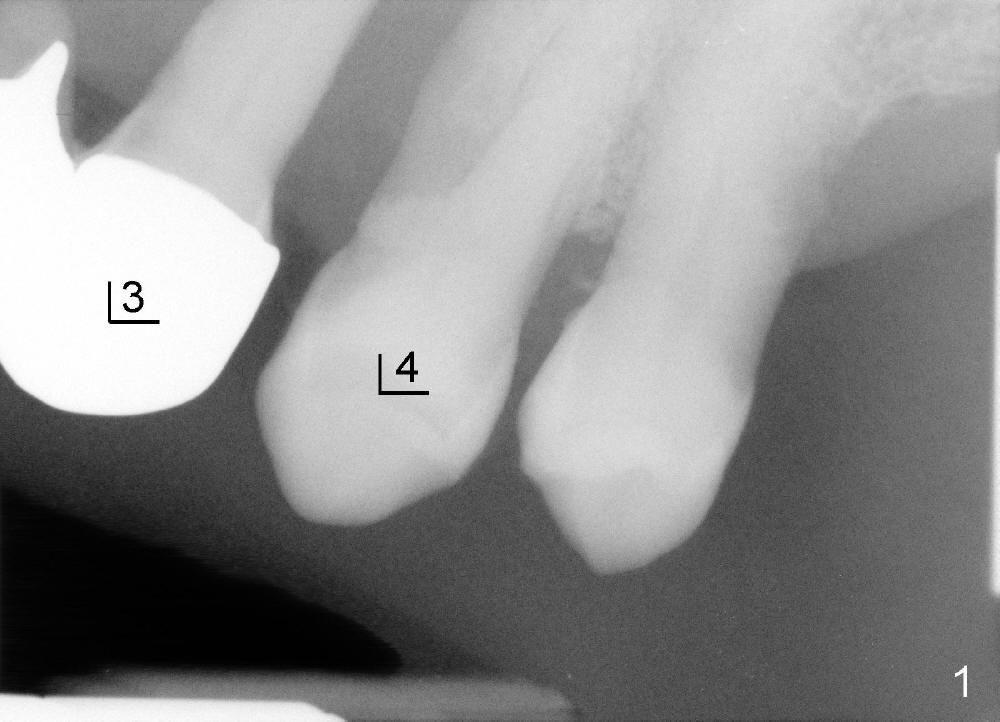

这种前臼齿牙根分布有点象上颌磨牙。颊侧两个根近远中宽度比鄂侧根宽(图四至图六),这个现象同样表现在X光片上(回到图一,图二),图七,图八是图一,图二放大,显示颊侧根(MB和*)比鄂侧根(P)宽,图八红线代表颊侧根根尖,黑线鄂侧根根尖。